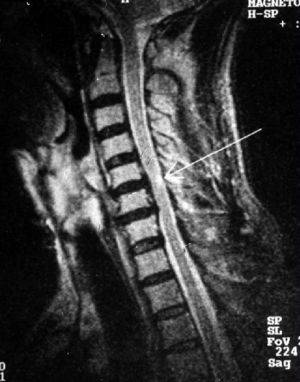

Наиболее грозным осложнением стеноза шейного отдела позвоночника является нарушение кровообращения в спинном мозге, т.н. «миелопатия» спинного мозга. (Рис.2)

Рис.2. Магнитно-резонансная томография (МРТ) шейного отдела позвоночника в сагиттальной проекции. Стеноз позвоночного канала на уровне С5-С6, С6-С7 позвонков. Стрелкой указан очаг миелопатии округлой формы на уровне диска С5-С6 позвонков.